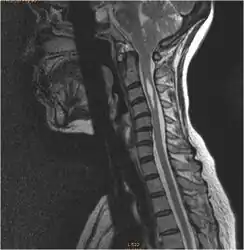

Diagnosis is made through a combination of patient history, neurological examination, and medical imaging.[14] Magnetic resonance imaging (MRI) is considered the preferred imaging modality for Chiari malformation.[15] The MRI visualizes neural tissue such as the cerebellar tonsils and spinal cord as well as bone and other soft tissues. CT and CT myelography are other options and were used prior to the advent of MRI, unfortunately the resolution of CT based modalities do not characterize syringomyelia and other neural abnormalities as well.

By convention, the cerebellar tonsil position is measured relative to the basion-opisthion line, using sagittal T1 MRI images or sagittal CT images.[16] The selected cutoff distance for abnormal tonsil position is somewhat arbitrary, as not every person will be symptomatic at a certain amount of tonsil displacement, and the probability of symptoms and syrinx increases with greater displacement; however, greater than 5 mm is the most frequently cited cutoff number, though some consider 3–5 mm to be "borderline,"; pathological signs and syrinx may occur beyond that distance.[16][17][18] One study showed little difference in cerebellar tonsil position between standard recumbent MRI and upright MRI for patients without a history of whiplash injury.[13] Neuroradiological investigation is used to first rule out any intracranial condition that could be responsible for tonsillar herniation. Neuroradiological diagnostics evaluate the severity of crowding of the neural structures within the posterior cranial fossa and their pressure against the foramen magnum. Chiari 1.5 is a term used when both brainstem and tonsillar herniation through the foramen magnum are present.[19]